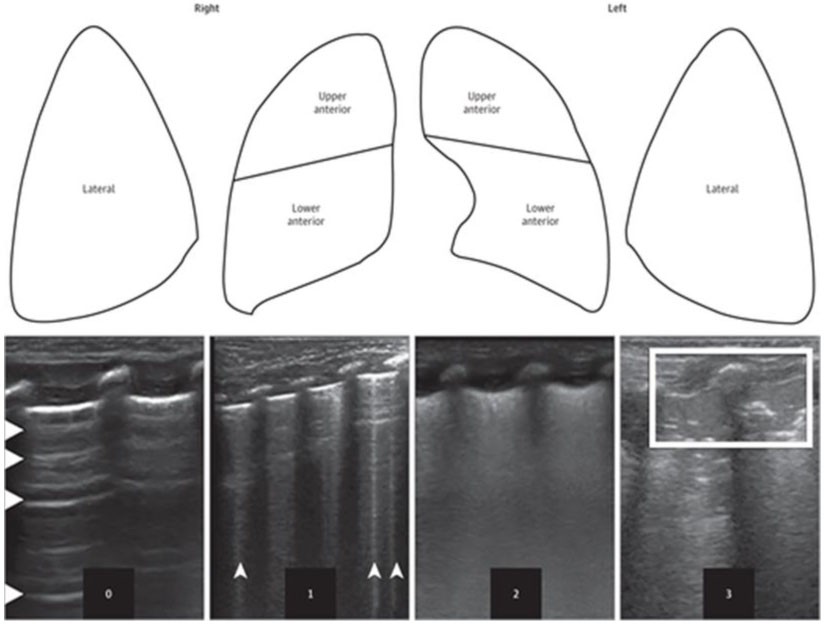

- Рекомендуется новорожденному ребенку с дыхательными нарушениями селективное проведение ультразвукового исследования легких для выявления признаков РДС при наличии возможностей медицинской организации [57 - 59].

Уровень убедительности рекомендаций C (уровень достоверности доказательств - 5).

Комментарий: см. Приложение Г3. Оценка состояния паренхимы по ультразвуковой шкале легких LUS или eLUS.

Данная шкала позволяет:

- дифференцировать респираторный дистресс-синдром (РДС) и транзиторное тахипноэ новорожденных (ТТН). РДС характеризуется плохо аэрируемым легким с отсутствием A-линий, наличием небольших "субплевральных" консолидаций и диффузным белым легким (сливающиеся B-линии). Напротив, при ТТН интерстициальный рисунок чередуется с областями почти нормального легкого (с A-линиями) [57].

- оценить степень тяжести РДС [59 - 61];

- уточнить показания для введения экзогенного сурфактанта [62];

- оценить риски развития БЛД.